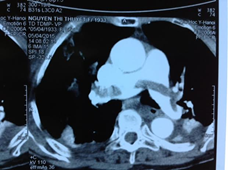

Theo báo cáo của tác giả Hoàng Bùi Hải và cs, Bệnh viện Đại học Y Hà Nội, tại Hội nghị tim mạch toàn quốc lần 14, đã ghi nhận 10 ca được áp dụng thuốc alteplase liều thấp 0,6mg/kg truyền trong 15 phút cho các bệnh nhân TĐMP cấp có rối loạn huyết động hoặc có rối loạn chức năng thất phải. Tuổi bệnh nhân thấp nhất là 27, cao nhất là 95 tuổi. Kết quả cho thấy tất cả các bệnh nhân đều thoát sốc nhanh, cải thiện nhanh huyết động, hô hấp. Hình ảnh kích thước huyết khối giảm nhiều, cải thiện nhanh chức năng thất phải sau 10 ngày điều trị kết hợp thuốc chống đông. Không có trường hợp nào bị chảy máu lớn. Chúng tôi khuyến cáo nên dùng phác đồ alteplase liều thấp 0,6mg/Kg cân nặng truyền tĩnh mạch ngoại vi trong 15 phút, tối đa 50mg cho các bệnh nhân TĐMP cấp có chỉ định [13] (Bảng 3.2).

Hình 3.1. Trước tiêu sợi huyết liều 0,6mg/kg (12.03)

| Hình 3.2. Sau tiêu sợi huyết 0,6mg/kg (20.03)